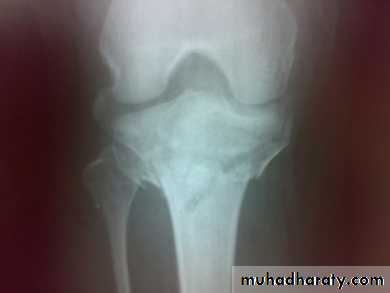

Tibial plateau fractures:Direct blow or fall from height may cause fracture of one tibial condyle or both. Fracture lateral condyle is the commonest named as bumper fracture caused by a force that abducts the tibia upon femur while the foot is fixed on ground. Patient usually is an adult, the knee joint is swollen, bruises, there is diffuse tenderness and doughy feel of haemarthrosis.ligaments injuries must be excluded.

Imaging : X-ray: anteroposterior, lateral & oblique

views. ct -Scan may used to detect amount of depression and comminuation.

Tibial plateau fracture